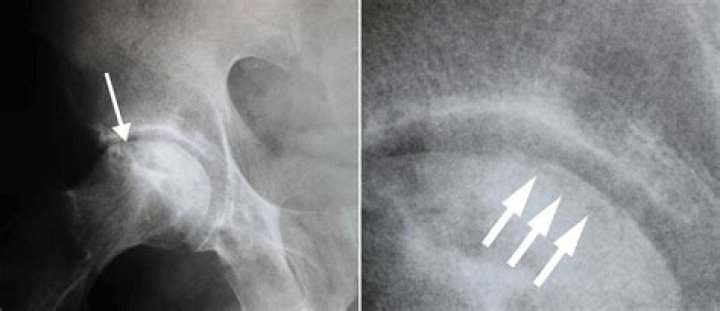

X-rays. They can reveal bone changes that occur in the later stages of avascular necrosis. In the condition's early stages, X-rays usually appear normal.

What does osteonecrosis look like on xray?

Imaging of osteonecrosis is frequently diagnostic with a serpentine rim of sclerosis on radiographs, photopenia in early disease at bone scintigraphy, and maintained yellow marrow at MR imaging with a serpentine rim of high signal intensity (double-line sign) on images obtained with long repetition time sequences.

Avascular necrosis (AVN) of hip